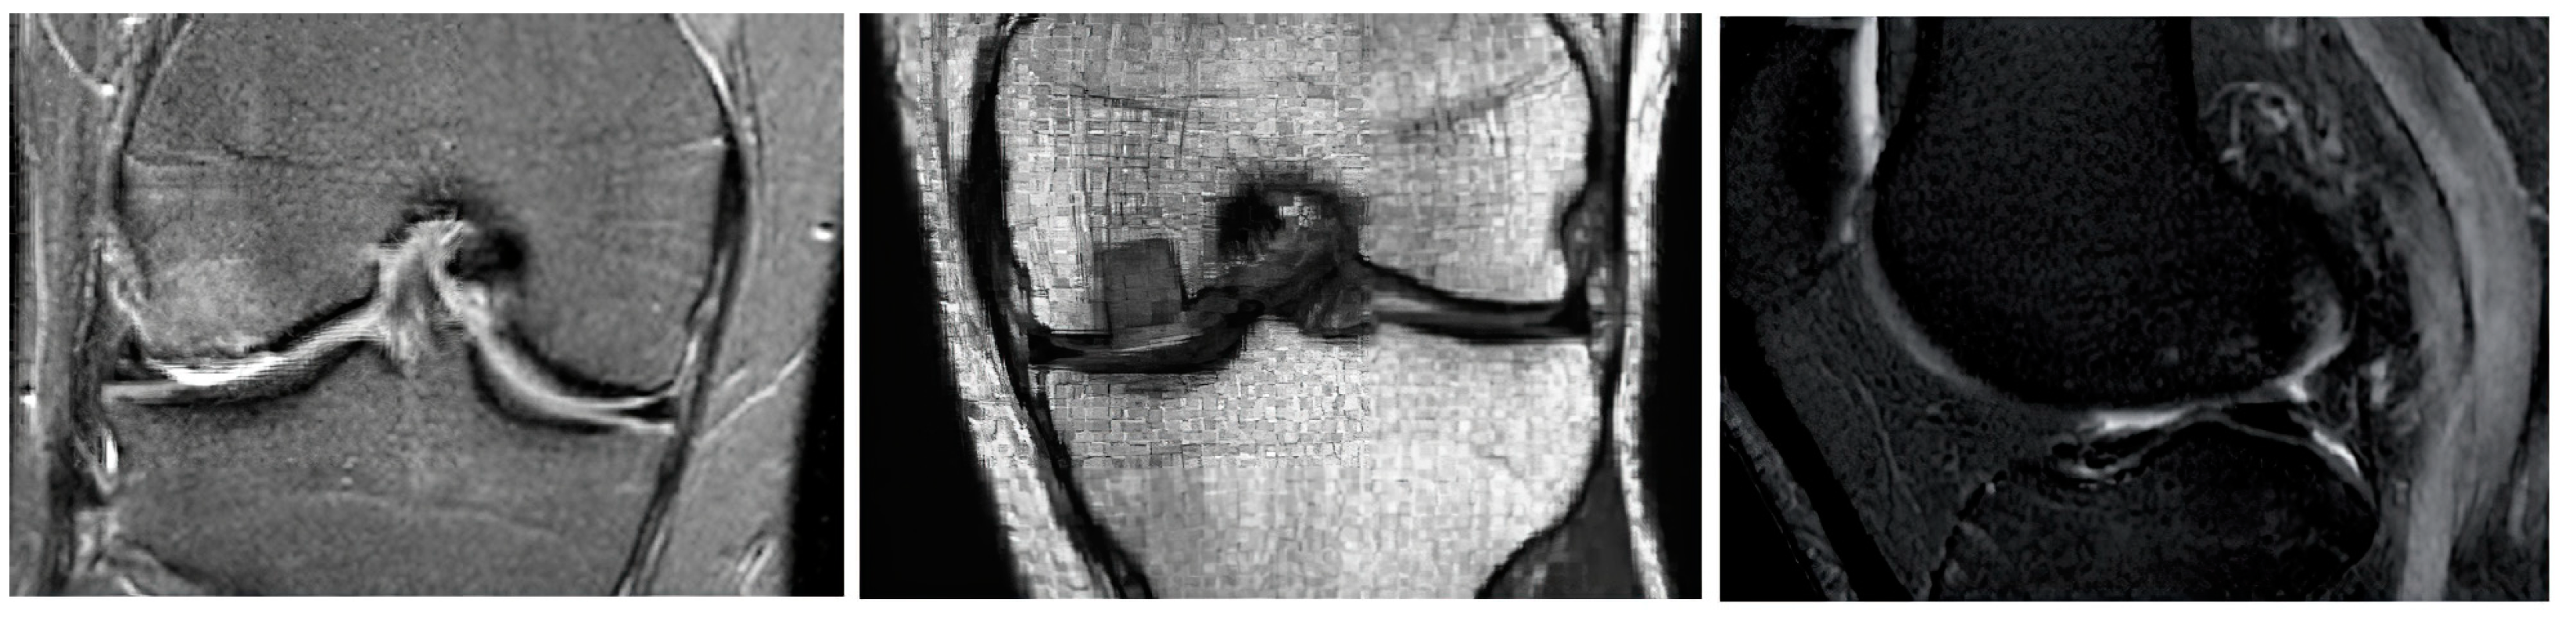

Furthermore, we introduce the graphical comparisons (Figure 4, Figure 5 and Figure 6) of the noise influence on segmentation performance. As we outlined earlier, we designed the analysis, which evaluates the dynamical effect of the noise influence on the segmentation performance. For this purpose, we used three noise generators: Gaussian, Speckle, and Salt and Pepper noise with variable intensity.

Figure 4. Examples of multiregional segmentation maps for optimized clustering schemes with a genetic algorithm (GA) and a PSO with K-means and FCM-based clustering for 4 regions where segmentation is influenced by Gaussian noise with 3 various intensity levels: σ 2 = 0.01 ,   μ = { 0.01 ,   0.1 ,   0.2 } .

Figure 5. Examples of multiregional segmentation maps for optimized clustering schemes with a genetic algorithm (GA) and a PSO with K-means and FCM-based clustering for 4 regions where segmentation is influenced by Speckle noise with 3 various intensity levels: σ 2 = { 0.01 ,   0.1 ,   0.2 } .

Figure 6. Examples of multiregional segmentation maps for optimized clustering schemes with a genetic algorithm (GA) and a PSO with K-means and FCM-based clustering for 4 regions where segmentation is influenced by Salt and Pepper noise with 3 various intensity levels: d = { 0.01 ,   0.1 ,   0.2 } .

Judging by a visual comparison of individual noise generators, the higher the applied noise intensity, the higher the influence on segmentation performance. Nevertheless, just based on the visual comparison, the differences among individual noise types are notable. Significant differences are notable between Speckle and Gaussian noise on the one side and Salt and Pepper noise on the other side, where noise has a higher impact on the segmentation performance. This is caused by the impulse character of the noise, which worsens segmentation performance.